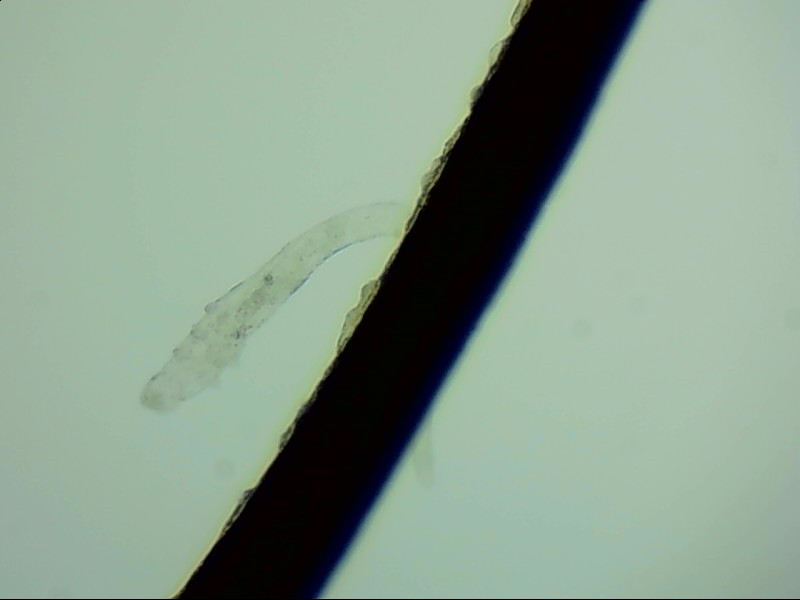

小張是一位程序員,長(zhǎng)時(shí)間對(duì)著電腦,感覺眼干、有異物感在所難免。最近他除了眼干、難受,還發(fā)現(xiàn)眼睛發(fā)癢,掉落的睫毛上還會(huì)帶著絲狀的分泌物。剛發(fā)現(xiàn)時(shí)小張并沒有放在心上,但當(dāng)他在屏幕上看到睫毛上的螨蟲時(shí),他的心里一陣后怕,“原來我的睫毛上長(zhǎng)著這么可怕的東西。”

螨蟲怎么會(huì)爬到睫毛里?廈門眼科中心蠕形螨性瞼緣炎門診張麗穎博士后介紹,人體螨蟲主要有兩種,一種是皮脂螨,主要寄生于皮脂腺和瞼板腺內(nèi);另一種是蠕形螨,“住”在睫毛毛囊里,晚上從毛囊里爬出來,白天躲在毛囊里產(chǎn)卵。

據(jù)介紹,這種疾病確診主要通過觀察睫毛里的螨蟲數(shù)量聯(lián)合瞼緣及眼表情況共同診斷。一般而言,如果12根睫毛里,有2條或是超過2條的螨蟲就可以被確診。如果檢查確實(shí)發(fā)現(xiàn)較多的蠕形螨感染,建議加上抗螨治療。張麗穎說,發(fā)現(xiàn)眼睛干澀、發(fā)癢,不要自行用藥,建議到醫(yī)院就診。如果長(zhǎng)期反復(fù)多發(fā)霰粒腫,要考慮是否存在蠕形螨感染。